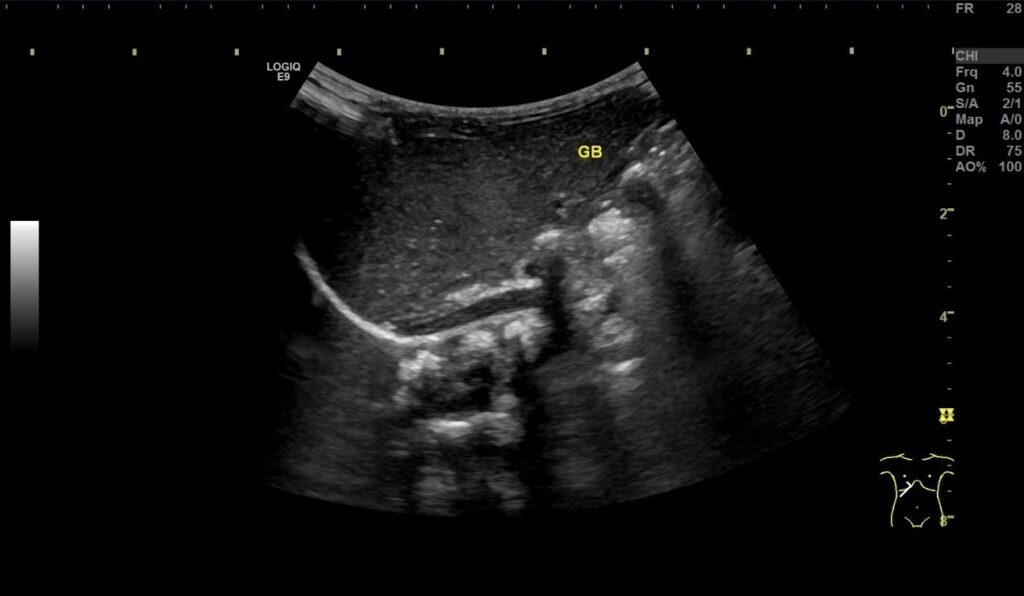

醫師為這名剛出生不久的新生兒經過檢查發現直接膽黃素數值為3.55 mg/dl (新生兒正常值:小於1.0 mg/dl),顯示其患有膽汁鬱積症,膽汁幾乎淤積在肝臟內,嚴重可能會造成肝硬化。腹部超音波檢查發現,即使在禁食六小時後,膽囊還是呈現細小狀態(正常禁食的情況下,應看到膽囊脹大),進一步確定膽汁無法正常流通。

剛出生兩週的嬰兒出現膽道閉鎖的情形。中醫大附醫提供